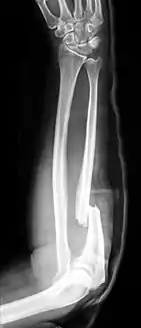

كسر مونتيجيا كسر في الزند يصيب المفصل مع الكعبرة.[1][2][3] وبشكل أدق هو كسر في الثلث القريب من الزند مع خلع في رأس الكعبرة. سمي نسبة إلى جيوفاني باتيستا مونتيجيا.

![]() صورة أشعة لكسر مونتيجيا في الساعد الأيمن. صورة أشعة لكسر مونتيجيا في الساعد الأيمن. | |